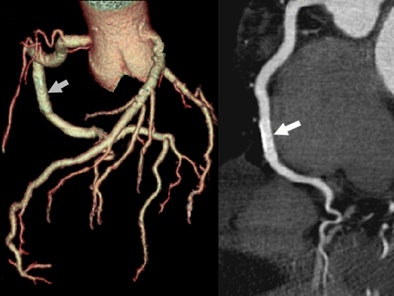

| A 55-year-old man presented with chest pain and history of a 3-year-old right coronary artery (RCA) stent. CTA effective dose using prospectively gated axial (PGA) technique was 0.90 mSv. Volume-rendered image of the coronary tree left depicts the stent (arrow) and many side branches. On the right a curved multiplanar reformatted image of the RCA depicts a widely patent 3.0-mm drug-eluting stent (arrow). |